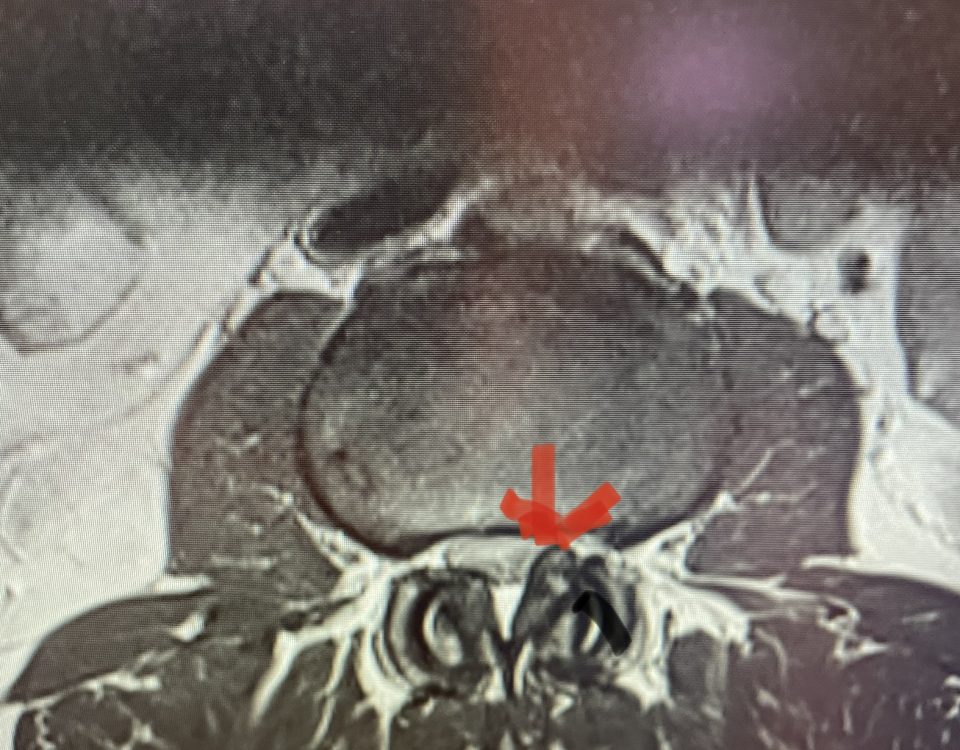

The spinal synovial cyst is one of the most interesting expressions of spinal instability. They emanate from the synovial lining of a degenerated facet joint that […]

People are obsessed with cysts! When you think about it, the body likes to form cysts. Why does this happen? Cysts can form just about anywhere […]